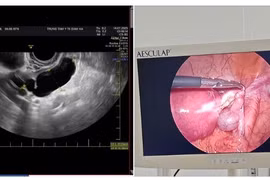

Cơn đau bụng bất thường không ngờ xoắn vòi tử cung hiếm gặp

Bệnh viện Phụ Sản Hà Nội vừa cấp cứu thành công ca xoắn vòi tử cung hiếm gặp cho người phụ nữ ở Hà Nội.